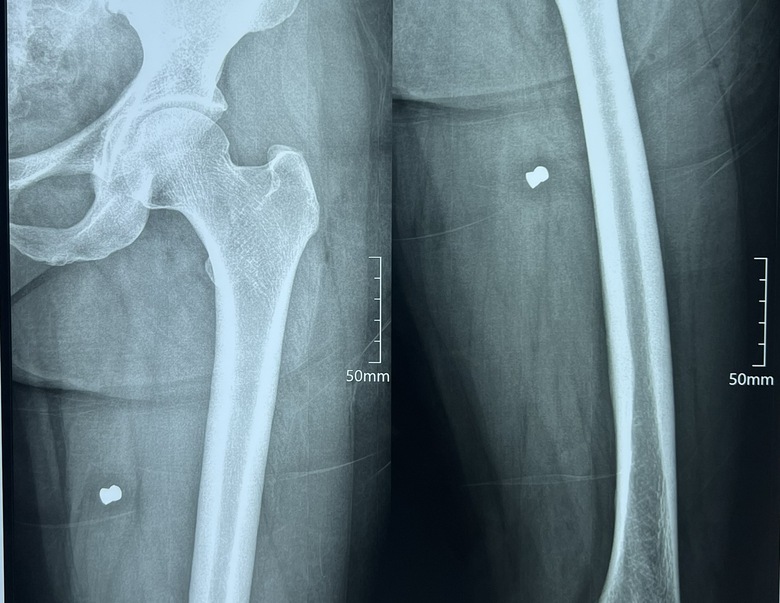

Phim X-Quang cho thấy dị vật kim khí găm bên trong chân của nữ công nhân Lê Thị Minh Khải.

Theo hình ảnh chụp phim X-Quang, nữ công nhân Võ Thị Lưu bị một vết thương hở rộng 1,5cm bên mặt ngoài đùi trái 1/3. Bên trong đùi có một vật kim khí.

Nữ công nhân Lê Thị Minh Khải có ba vết thương hở ở vùng ngoài da với mặt hở 1,5cm ở đùi chân trái, cẳng chân trái, bên trong vùng thịt có vật kim khí găm chặt.

Bác sỹ Nguyễn Quang, Phó giám đốc Bệnh viện Phúc Hưng cho biết, qua tiếp nhận hai trường hợp bệnh nhân nhập viện trong tình trạng có nhiều vết thương hở. Bước đầu thăm khám, chụp phim xác định nạn nhân bị vật kim khí găm chặt bên trong phần chân của hai bệnh nhân.

"Qua hội chẩn, kết quả chụp X-Quang, bệnh viện tiến hành gây mê và phẫu thuật lấy dị vật kim khí bên trong ra. Qua đó, xác định vật kim khí được lấy ra có hình giống đầu đạn với kích thước 1,1cm", bác sĩ Quang thông tin.

Kim khí có hình thù giống đầu đạn găm bên trong chân của nữ công nhân Lê Thị Lưu.